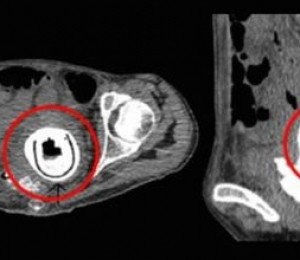

Dupa indepartarea chirurgicala a obiectului strain a venit si confirmarea: a fost vorba de o jucarie sexuala cu o lungime de 13 centimetri. Si obiectul se afla in vaginul ei de 10 ani.

Din cauza ca jucaria sexuala a fost blocata in corpul ei, femeia s-a confruntat cu o afectiune numita fistula vezico-vaginala (urina unei femei curge in vagin) si cu o alta afectiune numita uropatie obstructiva (un blocaj al vezicii urinare care determina urina sa se intoarca in rinichi).